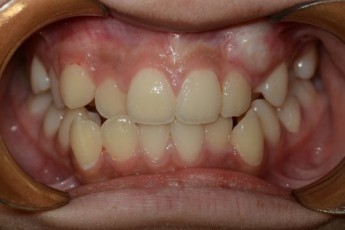

Before & After

Before

After